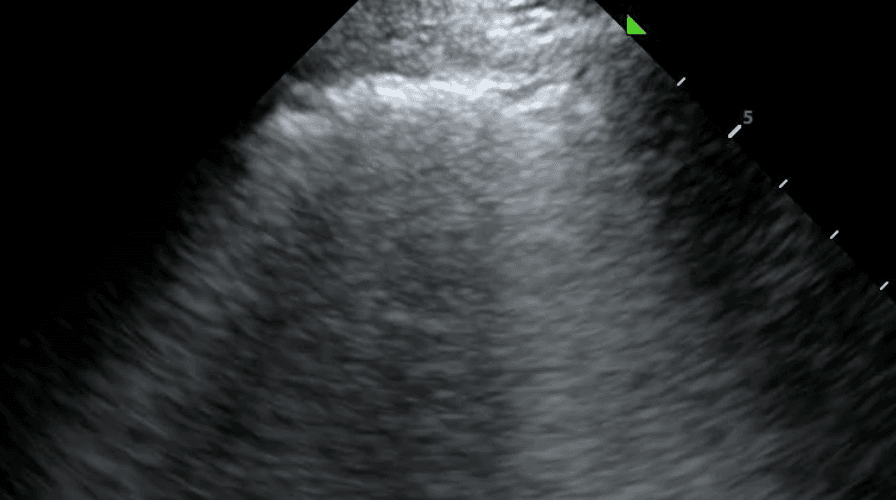

A normal pleural line is thin (less than 3 mm), smooth and continuous. In disease, the pleural line may be thickened or irregular. These characteristics can be combined with subpleural lesions and artifacts (such as A lines or B lines) to form a comprehensive differential diagnosis for lung pathology.

An irregular pleural line describes any disruption to the smooth, continuous appearance of the pleura. This can manifest as jaggedness, unevenness or fragmentation of the pleural line. Pleural thickening refers to a pleura that is thicker than 3mm. In the acute setting, an irregular or thickened pleural line points toward an infectious or inflammatory process such as pneumonia, acute respiratory distress syndrome (ARDS) or, less commonly, malignancy. For a more complete picture, pleural changes should be considered alongside other sonographic features including B lines, lung sliding and consolidation.